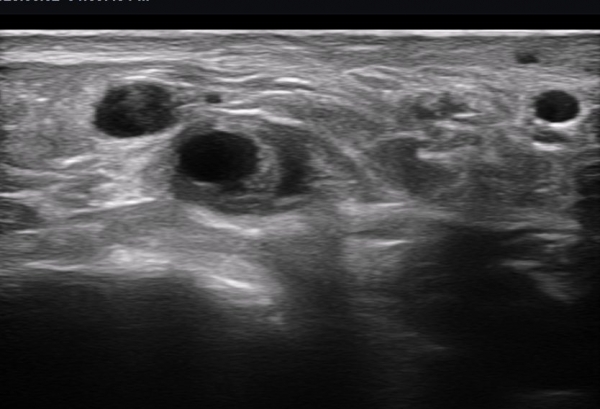

ÃÊÀ½ÆÄ ¼Ò°ß : ºñº¹½Å°æ Ⱦ´Ü¸é°Ë»ç¿¡¼­(»çÁø 1~13) ºñº¹½Å°æÀÇ Àú¿¡ÄÚ ºÎÁ¾°ú ´Üºñ°ñ°Ç³» ³¶Á¾¼º º´º¯ÀÌ °üÂûµÈ´Ù.

ºñº¹½Å°æ Á¾´Ü¸é°Ë»ç(»çÁø 14, 15)¿¡¼­ ºñº¹½Å°æÀÇ Àü¹ÝÀûÀÎ Àú¿¡ÄÚ ºÎÁ¾°ú ºñº¹½Å°æ ½ÉÃþÀ¸·Î ´Üºñ°ñ°Ç³»

³¶Á¾¼º º¯º¯ÀÌ °üÂûµÈ´Ù.